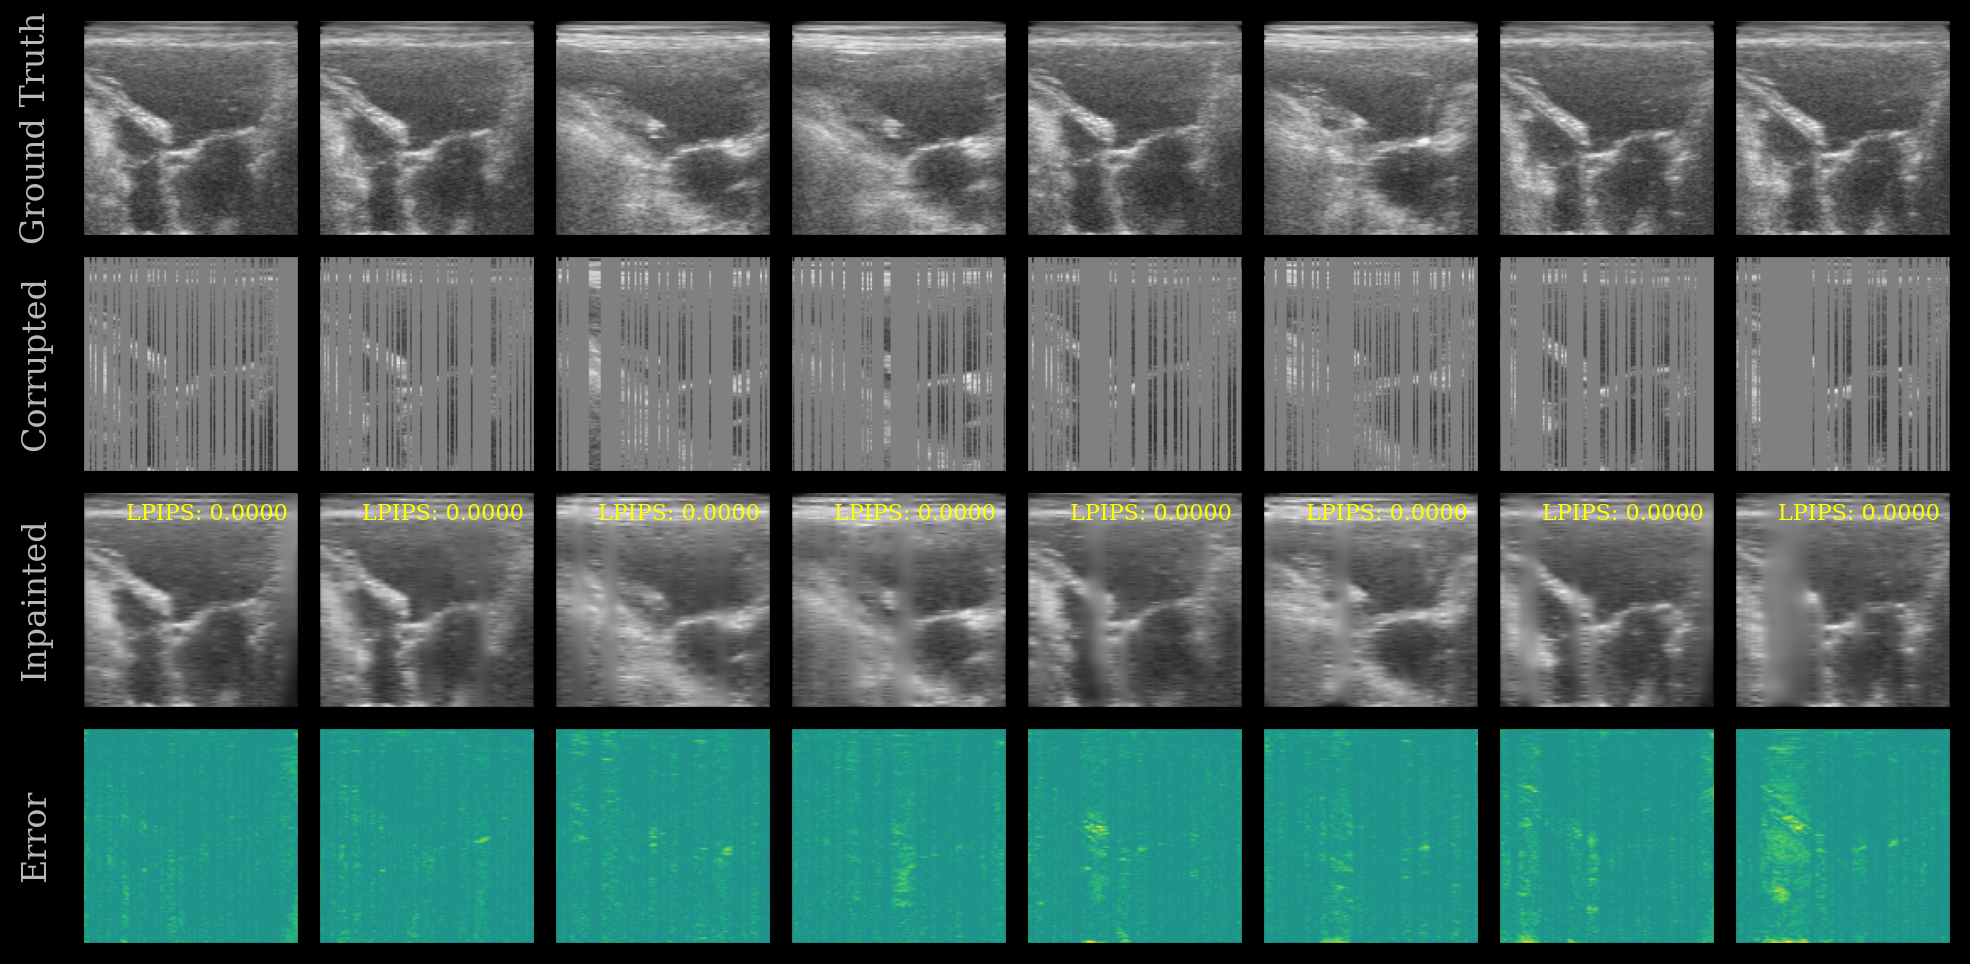

We plot the ground truth, corrupted, inpainted, and error images. The LPIPS score is shown on each inpainted image. Note that this model was trained on the EchoNet-Dynamic dataset, whereas we are testing now on the CAMUS dataset.

[10]:

error = ops.abs(batch - inpainted)

imgs = ops.concatenate([batch, corrupted, inpainted, error], axis=0)

imgs = ops.convert_to_numpy(imgs)

cmaps = ["gray"] * (3 * n_imgs) + ["viridis"] * n_imgs

fig, _ = plot_image_grid(

imgs,

vmin=-1,

vmax=1,

ncols=n_imgs,

remove_axis=False,

cmap=cmaps,

figsize=(n_imgs * 2, 6),

)

titles = ["Ground Truth", "Corrupted", "Inpainted", "Error"]

for i, ax in enumerate(fig.axes[: len(titles) * n_imgs]):

if i % n_imgs == 0:

ax.set_ylabel(titles[i // n_imgs])

# Show LPIPS score on each inpainted image

for ax, lpips_score in zip(fig.axes[n_imgs * 2 : 3 * n_imgs], lpips_scores):

ax.text(

0.95,

f"LPIPS: {float(lpips_score):.4f}",

ha="right",

va="top",

transform=ax.transAxes,

fontsize=8,

color="yellow",

fig.savefig("./inpainting_results.png", dpi=200, bbox_inches="tight")

UNet Inpainting Results